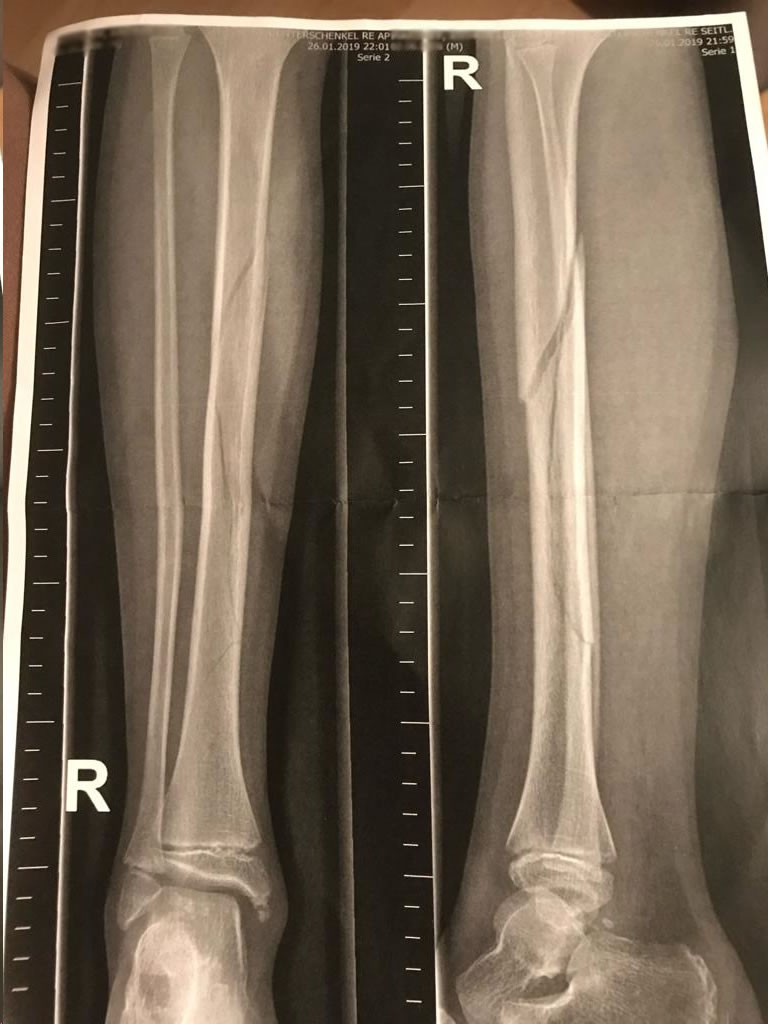

marcos79 hat geschrieben: 05.12.2023 - 20:27 Am meisten hat mir seine Mitleids tour mit Chrigel Junior genervt, der ja anscheinend ein gebrochenes Bein hatte. Nur komisch das ich die Zwei auf der Piste in St. Moritz zur selben Zeit gesehen habe....

Diese Unterstellung ist für mich schlicht unanständig☝️ Wann willst du die beiden den gesehen haben? Der Unfall war am 19. Januar 2019 und im April ging auf Ski für Ihn noch nix. Erster Skitag wieder in 2020🤔 Und ich hab die Bilder mit dem Gips gesehen, wer es nicht glauben will, siehe anbei; vielleicht arbeitest du mal an deiner Aufmerksamkeit oder deinem Gedächtnis?

IMG-20231205-WA0021.jpg

IMG-20231205-WA0021.jpg (135.02 KiB) 3686 mal betrachtet

IMG-20231206-WA0010.jpg

IMG-20231206-WA0010.jpg (96.61 KiB) 3686 mal betrachtet